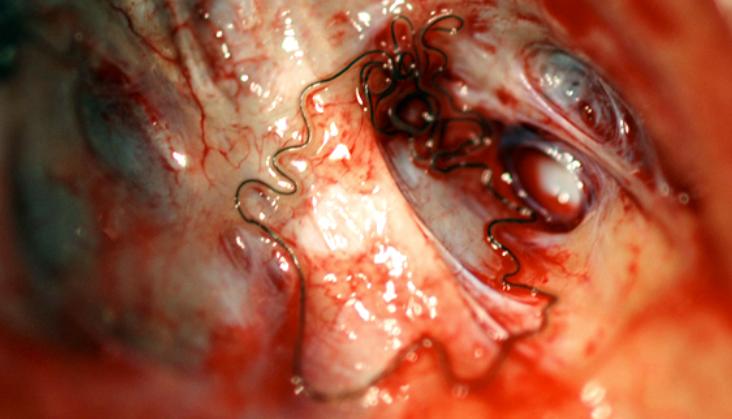

Parelaphostrongylus tenuis adult in deer brain (Meningeal worm)